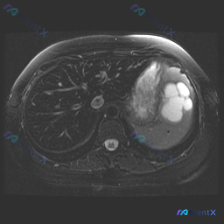

今天看到一份腹部MRI的T2WI图像,焦点在脾脏,整理一下读片的思考过程,避免踩坑。 先看核心影像表现 这是一张轴位T2WI,最突出的异常在脾脏: - 信号:脾实质内有数个类圆形极高信号影,信号强度接近脑脊液,提示是液体(浆液性为主)。 - 形态:边界清晰,但边缘呈分叶状,囊腔之间相互融合或紧邻,不...

最近看到一张腹部MRI的T2加权轴位片,最初的焦点是“脾脏病变”,但仔细梳理下来,觉得这个病例的阅片思路特别有借鉴意义,整理出来和大家分享。 先看病例的影像客观发现 - 肝脏:右叶可见一处类圆形高信号影,边界清晰锐利,信号均匀; - 脾脏:外后缘可见一处类圆形高信号影,边界清晰,信号均匀; - 左肾...

看到一份很有意思的影像读片案例,用户的问题聚焦在“脾脏病变”,但影像本身却给了我们一个完全不同的方向,整理一下思路和大家分享。 --- 先看影像基本情况 - 序列:腹部MRI T2加权轴位像 - 用户焦点:脾脏病变 关键影像发现(按实际读片顺序) 1. 肝脏、胆囊、胰腺:未见明显异常信号或肿块,胆管...